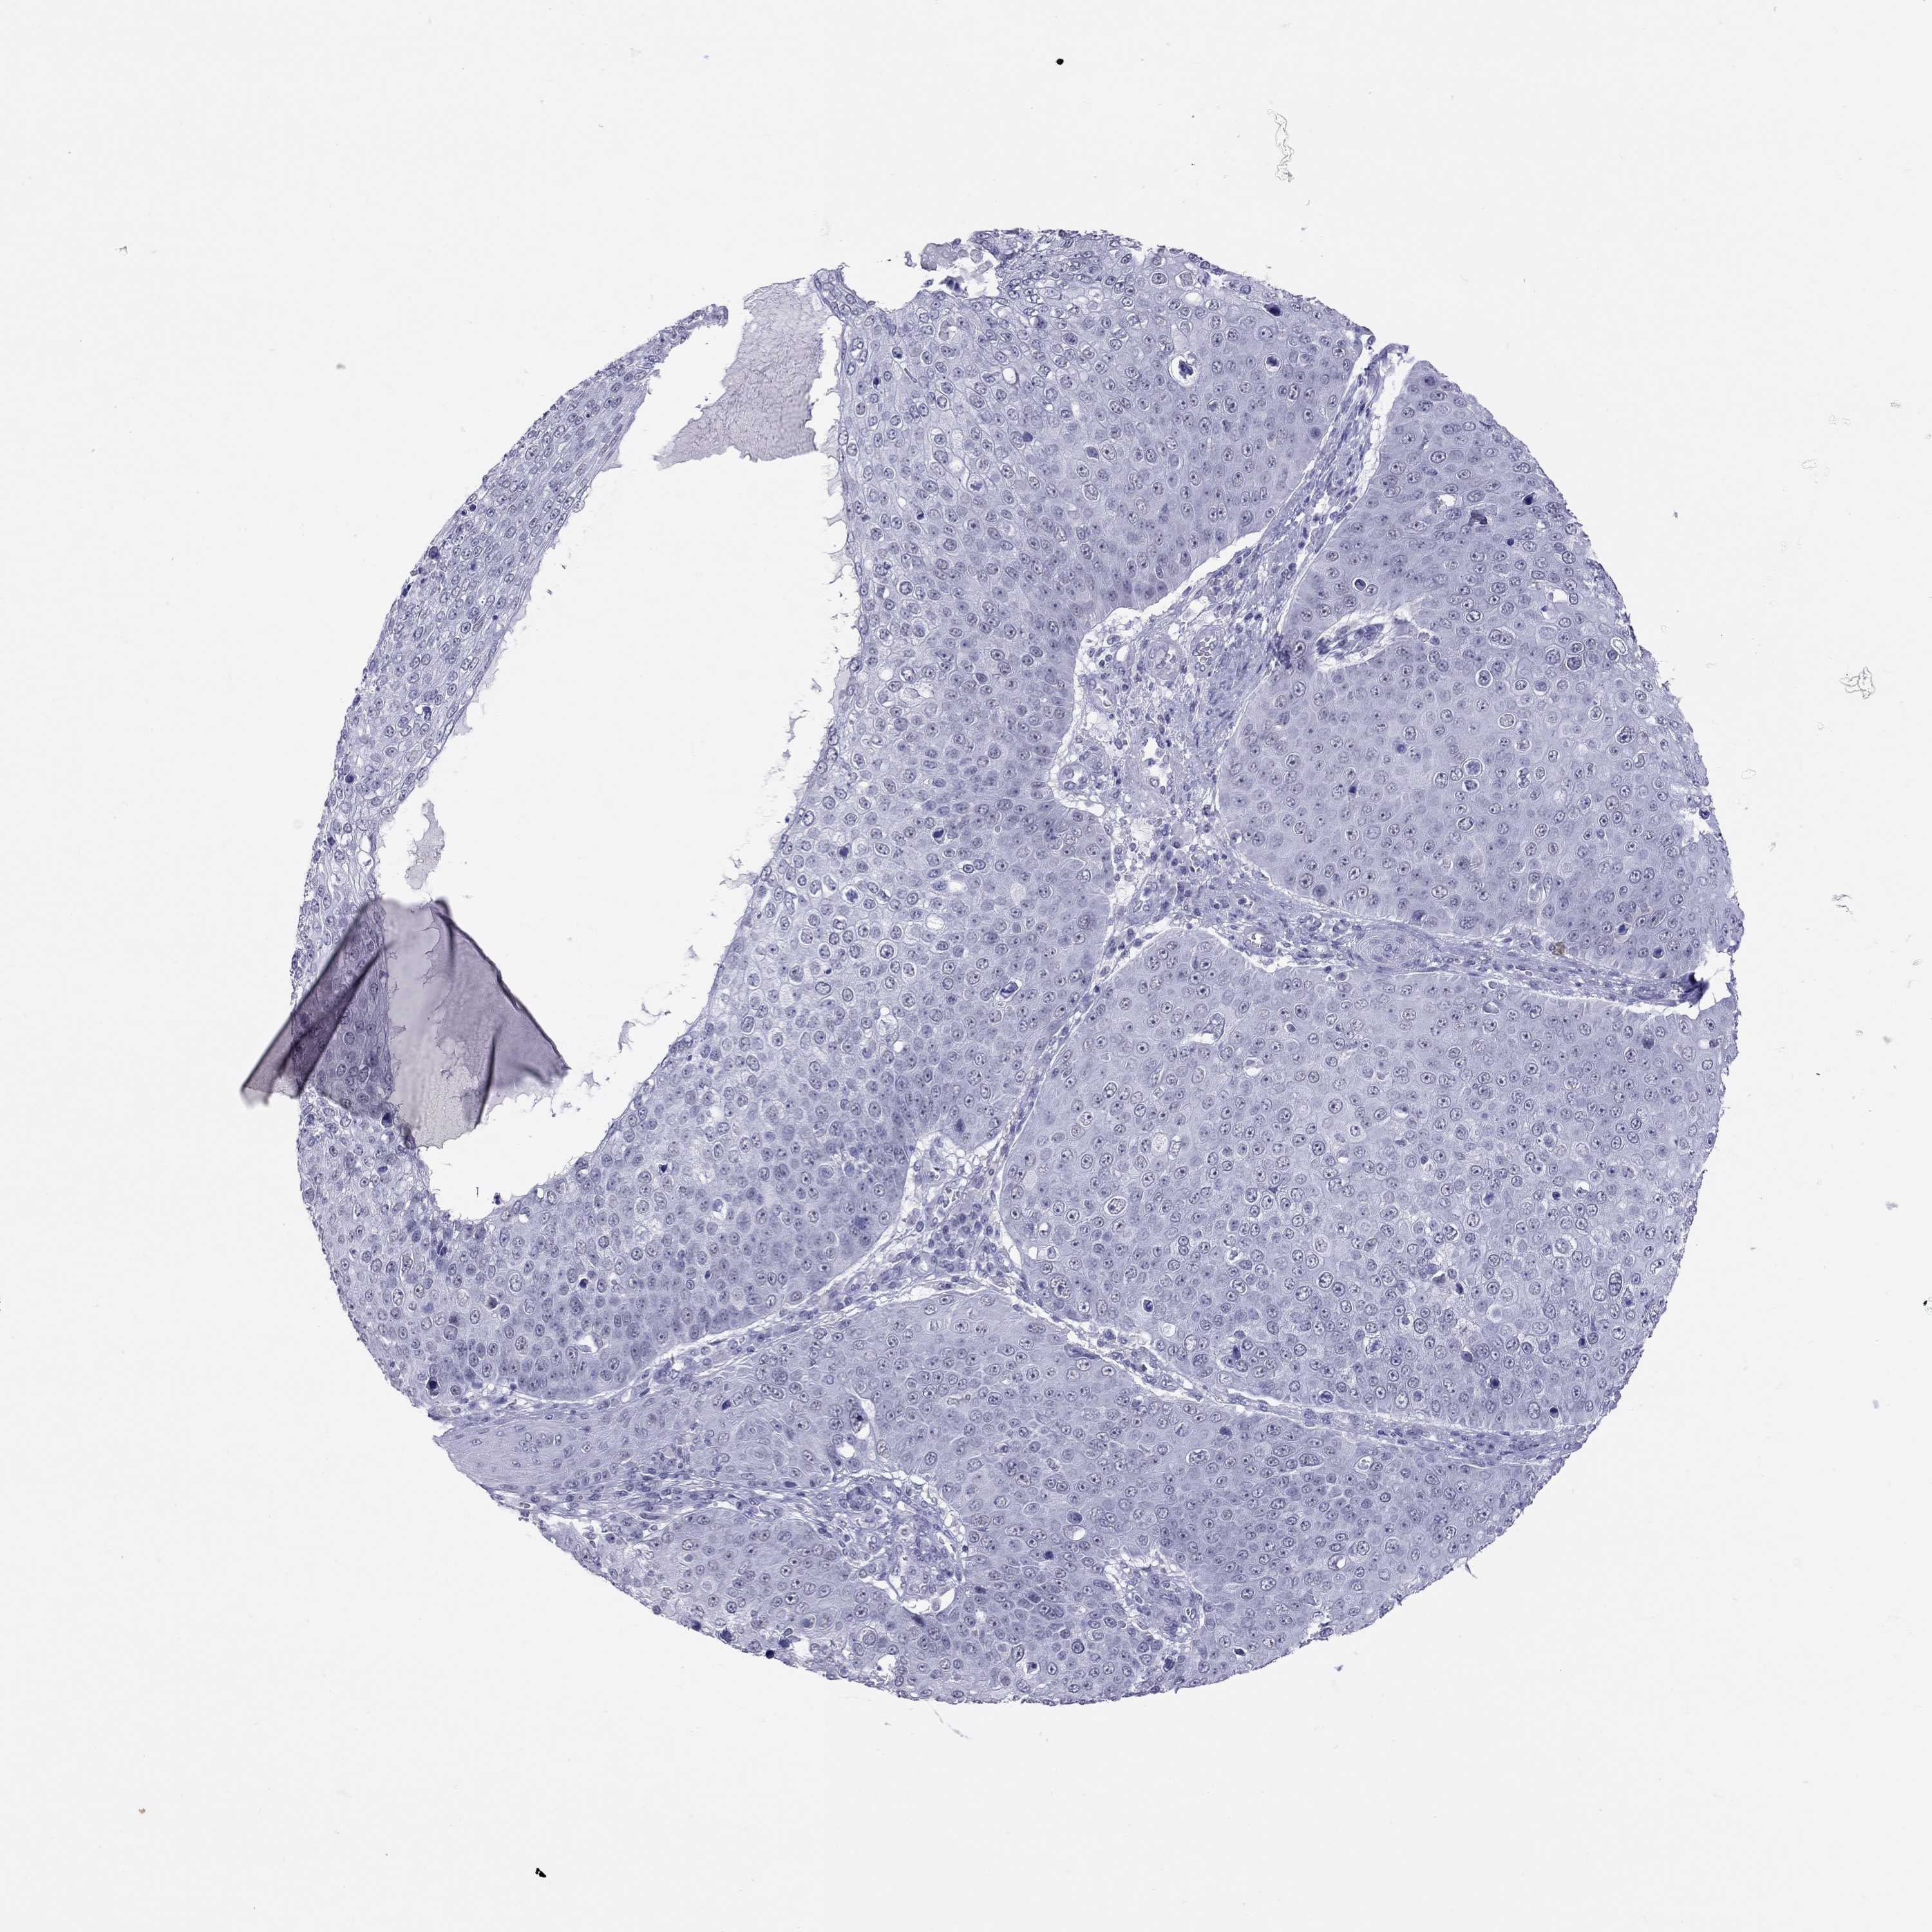

Basal cell and squamous cell cancer

SKIN CANCER - Protein expressioni

A mouse-over function shows sample information and annotation data. Click on an image to view it in a full screen mode. Samples can be filtered based on level of antibody staining by selecting one or several of the following categories: high, medium, low and not detected. The assay and annotation is described here.

Each image is clickable and will lead to virtual microscopy that enables deeper exploration of all samples and also displays staining intensity scores, fraction scores and subcellular localization as well as patient and tissue information for each sample.

Antibody HPA077658

Basal cell carcinoma

Squamous cell carcinoma, NOS